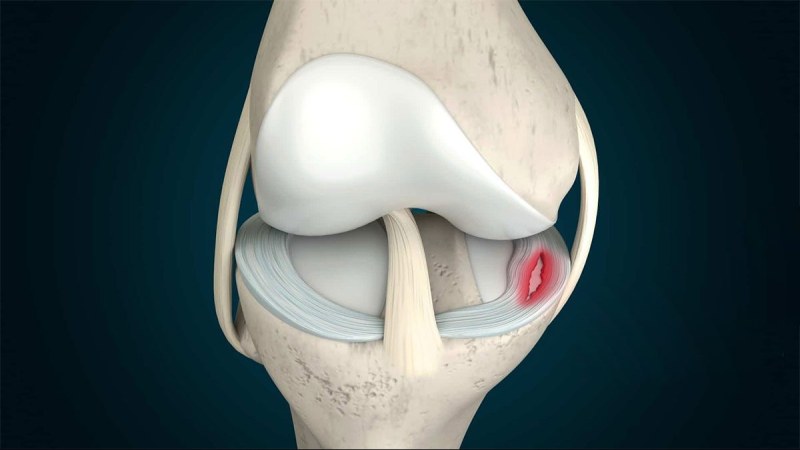

مینیسک زانو یک بافت غضروفی هلالیشکل است که در مفصل زانو قرار دارد و نقش اصلی آن، جذب فشار و توزیع وزن بدن روی مفصل زانو است. هر زانو، دو مینیسک داخلی و خارجی دارد. این ساختارها باعث پایداری مفصل، کاهش اصطکاک بین استخوانها و جلوگیری از آسیبدیدگی زانو میشوند. مینیسکها همچنین به توزیع مایع مفصلی کمک کرده و از ساییدگی استخوانها روی یکدیگر جلوگیری میکنند. با توجه به اهمیت مینیسک در عملکرد طبیعی زانو، آسیبدیدگی آن معمولا باعث درد، التهاب و محدودیت حرکتی میشود. پارگی یا فرسایش مینیسک اغلب در ورزشکاران و افراد مسن دیده میشود.

پارگی مینیسک زانو یکی از شایعترین بیماری های زانو است که معمولاً به دلیل پیچ خوردن ناگهانی زانو، چرخش شدید یا فشار زیاد روی مفصل رخ میدهد. این آسیب بیشتر در ورزشهایی مانند فوتبال، بسکتبال و اسکی دیده میشود. همچنین افزایش سن و تحلیل رفتن غضروفها، احتمال پارگی مینیسک را افزایش میدهد. جالب است بدانید افرادی که حرکات ناگهانی و پرفشار انجام میدهند یا دچار ضعف عضلانی در اطراف زانو هستند، بیشتر در معرض این آسیب قرار دارند. پارگی مینیسک ممکن است بهصورت جزئی یا کامل رخ دهد که هرکدام علائم و روشهای درمانی متفاوتی دارند.